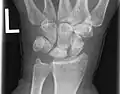

Radiographic classification

First described by David Lichtman et al. in 1977.[7] The purpose of this classification system is to guide treatment and to enable comparison of clinical outcomes.

1. Stage I Normal radiograph (possible lunate fracture).

2. Stage II Sclerosis of the lunate without collapse. (Portions of the lunate begin to deteriorate. This shows as a white blemish on x-rays.)

3. Stage IIIA Lunate collapse and fragmentation, in addition to proximal migration of the capitate.

4. Stage IIIB Lunate collapse and fragmentation, in addition to proximal migration of the capitate. In addition there is fixed flexion deformity of the scaphoid.

5. Stage IV Changes up to and including fragmentation, with radiocarpal and midcarpal arthritic changes.